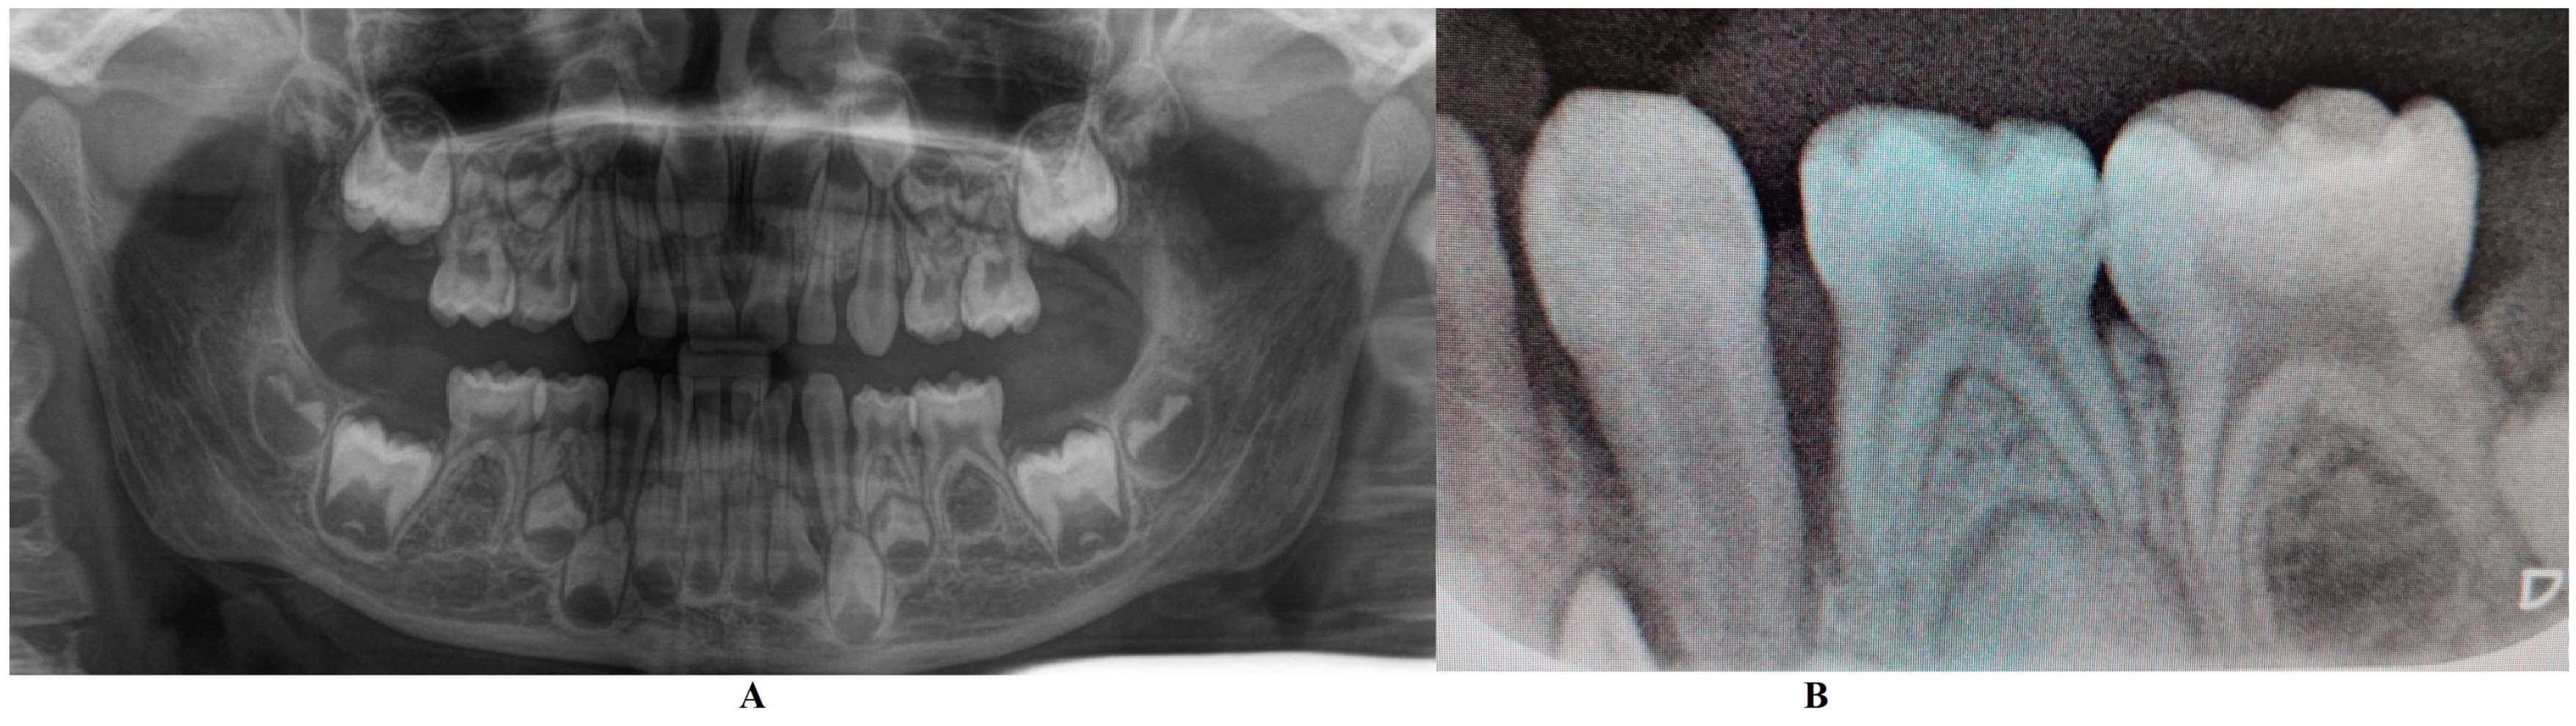

In the Periodontology Department (14 June), a full investigation was performed including one panoramic and retro-alveolar radiological examination (Figure 1). This radiological examination confirmed the localized nature of the bone loss with no visible signs of other disorders. The written results were pains of unclear origin, early temporary canine and bone loss, all caused by a possible metabolic disease (hypophosphatasia/hyperphosphatasia), with the recommendation to follow the metabolic–endocrinology path. The patient was sent to the Endocrinology Department for blood and genetic tests. No clinical signs of orthodontic problems (e.g., hyper-eruption) were found at this stage. No indication of treatment was given to the parents, except recall (i.e., after genetic and metabolic tests results) and prophylaxis (common oral hygiene).

Figure 1.

X-rays taken in the Periodontology Department of München University Hospital (early June): (A)—panoramic with localized bone loss around temporary lower left canine, (B)—retro-alveolar detailed X-ray of the same area.

The first diagnosis (of presumed hypophosphatasia/hyperphosphatasia) was established in the Periodontology Department of München University Hospital in the middle of June (14 June), despite the available radiographical examination acquired during the full clinical examination (Figure 1) and patient’s history (with no visible signs of disorder). The radiographical examination clearly showed a massive, localized bone loss around the temporary lower left canine (i.e., 7.3—Figure 1B) visible on the retro-alveolar X-ray, with no other visible radiological signs present upon panoramic X-ray (Figure 1A). During clinical examination, increased tooth movements were also present, with no other clinical signs (at least, after the parents’ report). Moreover, blood tests (19 June) showed normal levels of calcium, phosphate, natrium, and parathyroid hormone, and absence of hypercalciuria, which contradicts the hypophosphatasia/hyperphosphatasia diagnosis [20]. No other diagnosis or treatment approach was performed.

On the other hand, when the first Stage IV grade C localized periodontitis/LPP diagnosis was established (2 August), the clinical examination showed an increased mobility of the temporary lower left canine due to massive bone and periodontal ligament loss, associated with a localized inflammation of the free gingival margin around the tooth, and with small amounts of dental plaque due to difficulties with oral hygiene (Figure 2 and Figure 3). No other plaque deposits, inflamed gingiva, or teeth mobility issues were detected during the clinical examination. When this information was correlated with the radiological examination from two months prior (19 June, Figure 1), with localized bone loss, the diagnosis based on clinical and radiological data was confirmed, with no need for further radiological examination. Moreover, the blood test with higher levels of lymphocytes [2,14] also confirmed Stage IV grade C localized periodontitis/LPP diagnosis. To assess the periodontal pocket bacteria responsible for this atypical LPP case (i.e., temporary molars/incisors are usually involved [1,2,10], rather than the canine, as in this case), a canine periodontal sulcus secretion test was sampled and sent to the laboratory.

A rapid Stage IV grade C localized periodontitis/LPP diagnosis is essential, since the aggressive auto-immune response to bacteria can rapidly lead to a resorptive process [1,2,3,4,5,6,7,8,9,11]. Thus, a simple bacterial test to identify the pathogenic bacterium types would provide both diagnostic confirmation and justification for antibiotic treatment [2,3,11,12,13,14,15]. If LPP disorder is identified early, there is time to wait (i.e., usually up to two weeks) for lab test results, and only then should antibiotic therapy proceed [5,6,9,10,16,17,18]. However, if the LPP diagnosis is late (as it was herein), antibiotic treatment must be started, with a combination of two large-spectrum antibiotics (amoxicillin and metronidazole) to cover most bacterial types [5,6,9,10,16,17,18]. It must be emphasized that LPP usually comes without or with very few plaque deposits (as the case herein showed—see Figure 1, Figure 2, Figure 3 and Figure 4), with little influence over surrounding gingival inflammation [1,2,4,5,6,7,8,9,10].